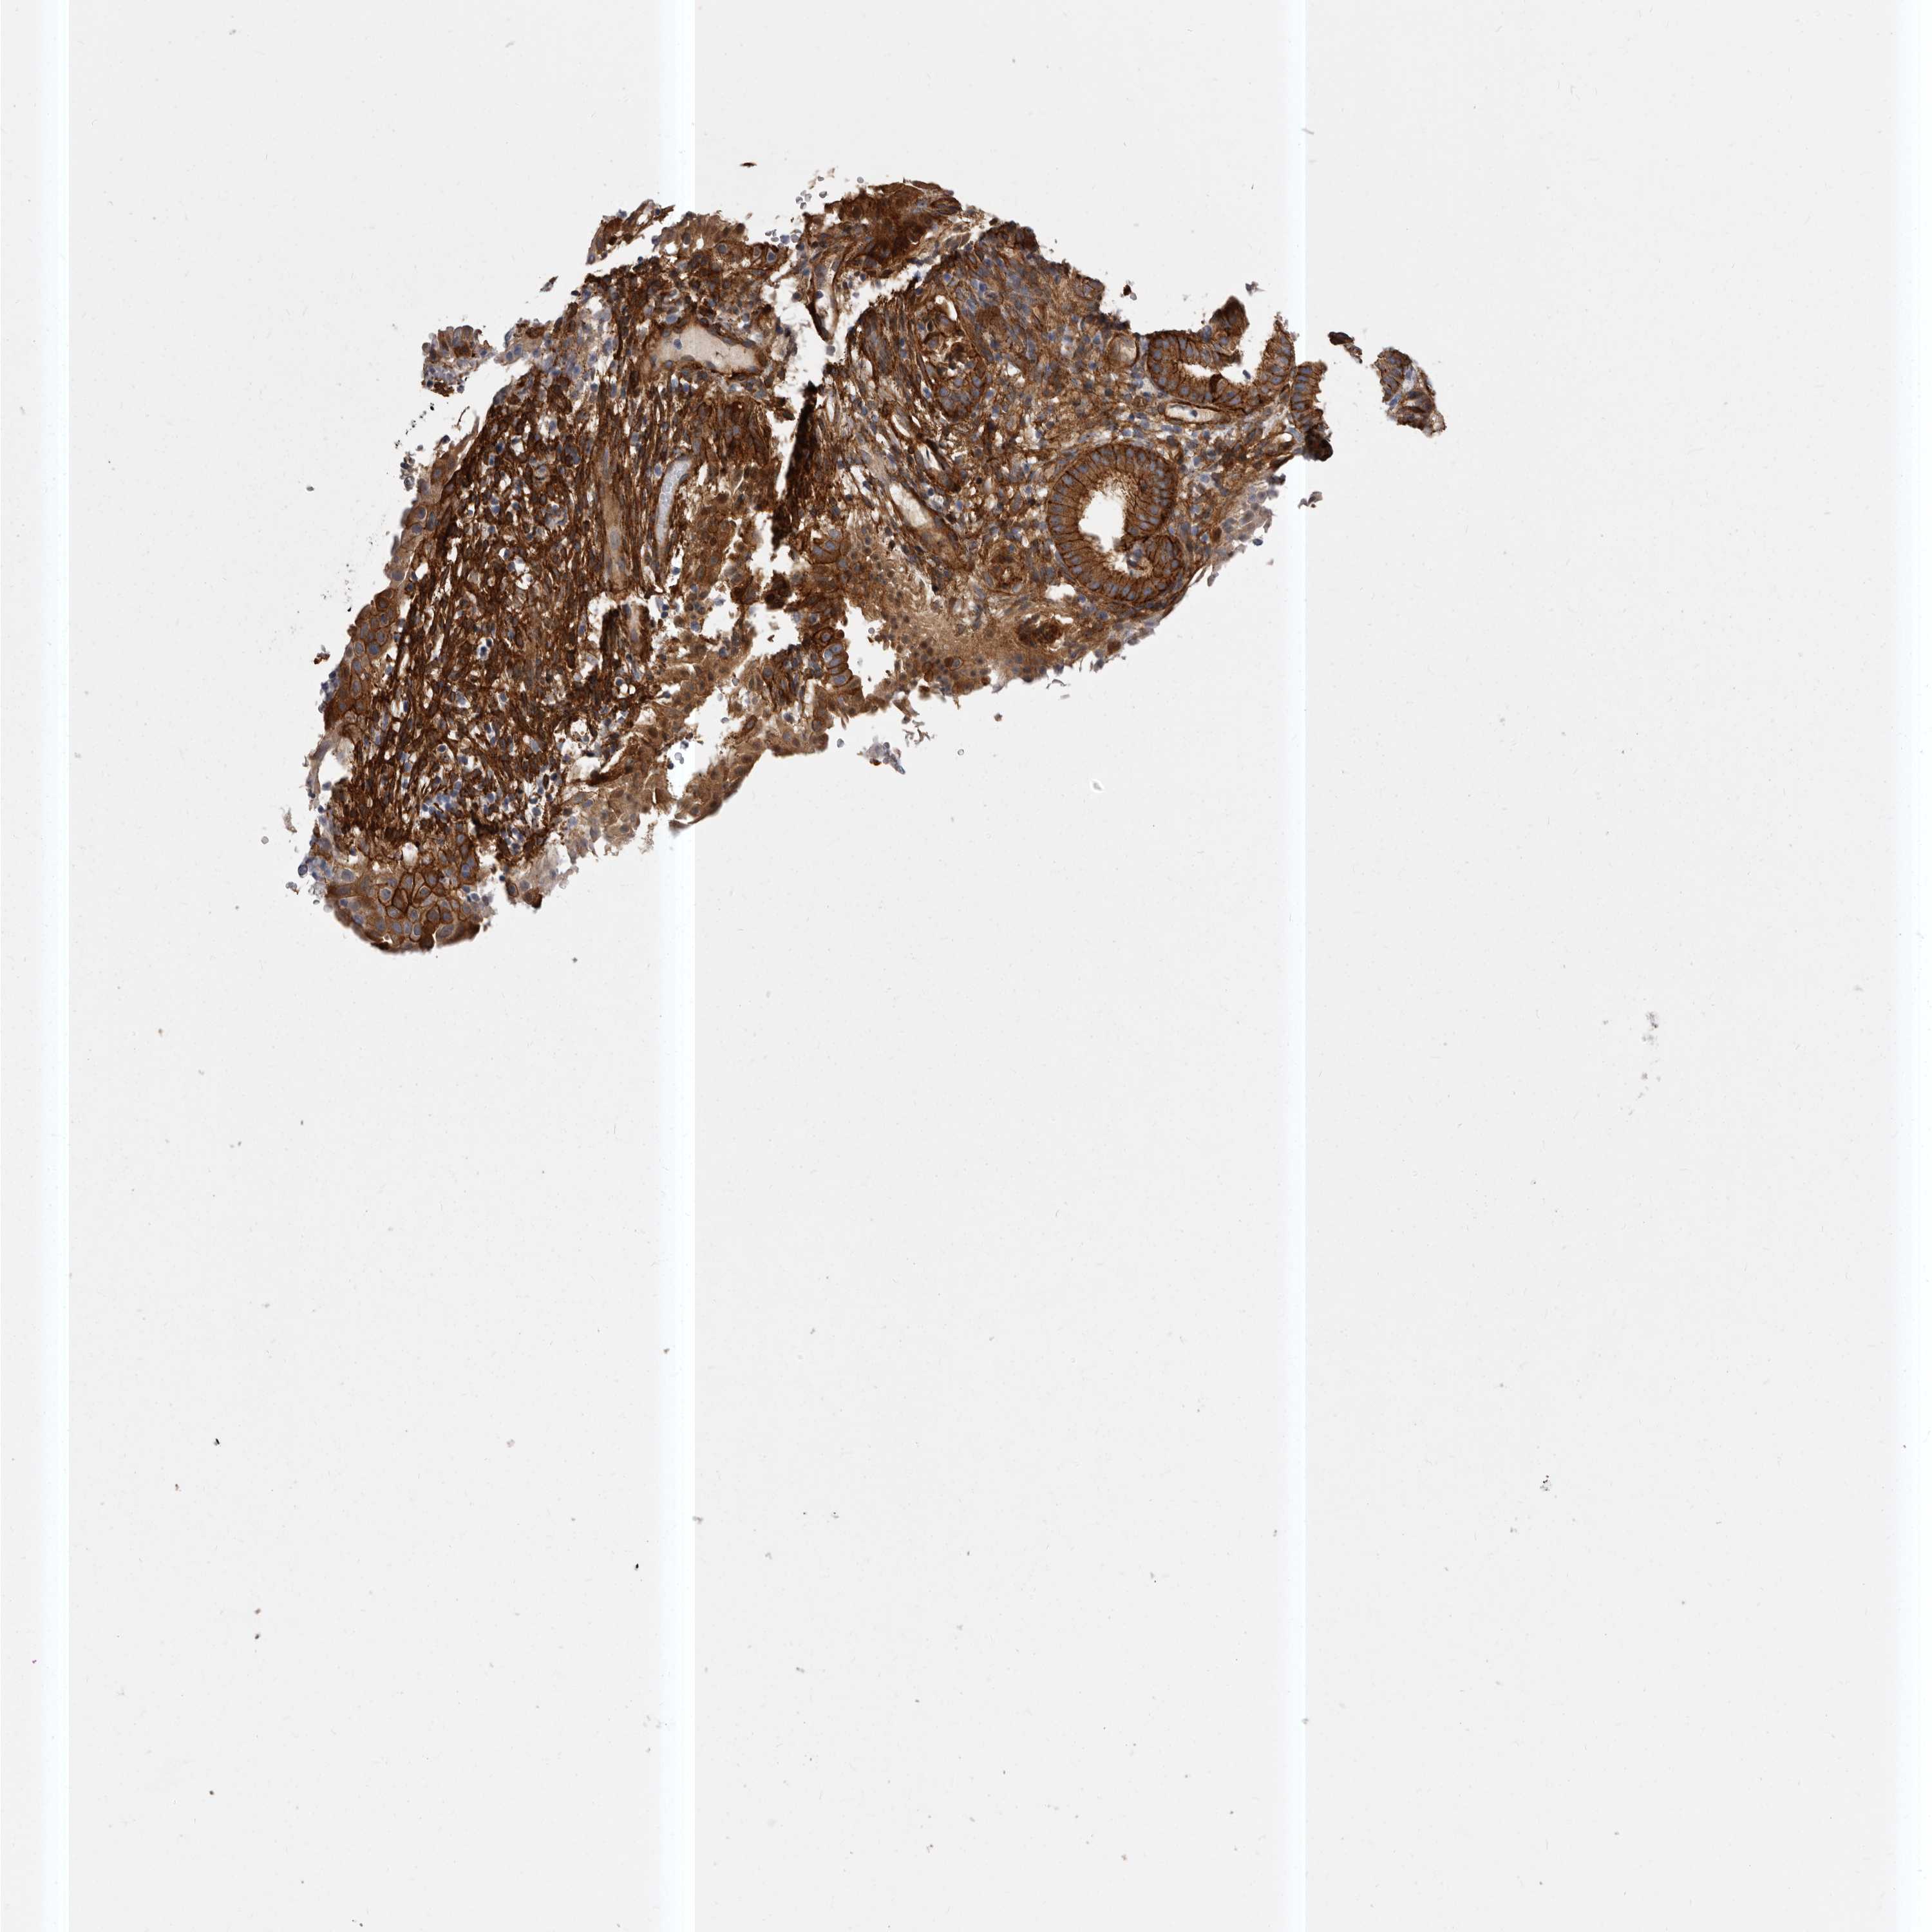

ENDOMETRIAL CANCER - Protein expressioni

A mouse-over function shows sample information and annotation data. Click on an image to view it in a full screen mode. Samples can be filtered based on level of antibody staining by selecting one or several of the following categories: high, medium, low and not detected. The assay and annotation is described here.

Note that samples used for immunohistochemistry by the Human Protein Atlas do not correspond to samples in the TCGA dataset.

Antibody stainingi

Antibody staining in the annotated cell types in the current human tissue is reported as not detected, low, medium, or high, based on conventional immunohistochemistry profiling in selected tissues. This score is based on the combination of the staining intensity and fraction of stained cells.

Each image is clickable and will lead to virtual microscopy that enables deeper exploration of all samples and also displays staining intensity scores, fraction scores and subcellular localization as well as patient and tissue information for each sample.

Antibody HPA028448

Antibody HPA028696

Staining

High

Medium

Low

Not detected

Intensity

Strong

Moderate

Weak

Negative

Quantity

>75%

75%-25%

<25%

None

Location

Nuclear

Cytoplasmic/membranous

Cytoplasmic/membranous,nuclear

Adenocarcinoma, NOS